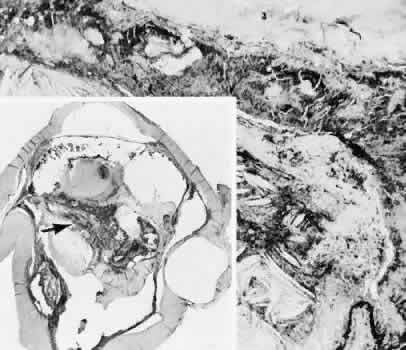

Infectious bacterial endophthalmitis (Figs. 39 and 40) usually presents early in the postoperative period.113,114 Pseudomonal and streptococcal organisms often cause rapid and total destruction of the eye. Organisms of especially low virulence, such as Staphylococcus epidermidis and Priopionibacterium acnes, may not present for months and may be misinterpreted as sterile endophthalmitis caused by a toxic reaction to intraocular lens materials or phacoanaphylactic endophthalmitis targeted to lens cortical remnants.115–117 Infectious endophthalmitispresenting months after surgery may be caused by a fungal infection or by bacteria of low virulence as pointed out above.

Fig. 39. A case of endophthalmitis following cataract extraction. A. An area of hypopyon inferiorly and a suture line secured with 8/0 silk sutures superiorly can be easily identified. The case is from the era of intracapsular cataract surgery, however, the risk of infection remains with all types of more recent procedures. B. In the histologic section an vitreous abscess in present. The lytic nature of bacterial infections has caused extensive gaping of the original limbal wound allowing herniation of inflamed intraocular tissue into the subconjunctival space. The retina is completely detached and necrotic. (Hematoxylin-eosin stain; × 5.)